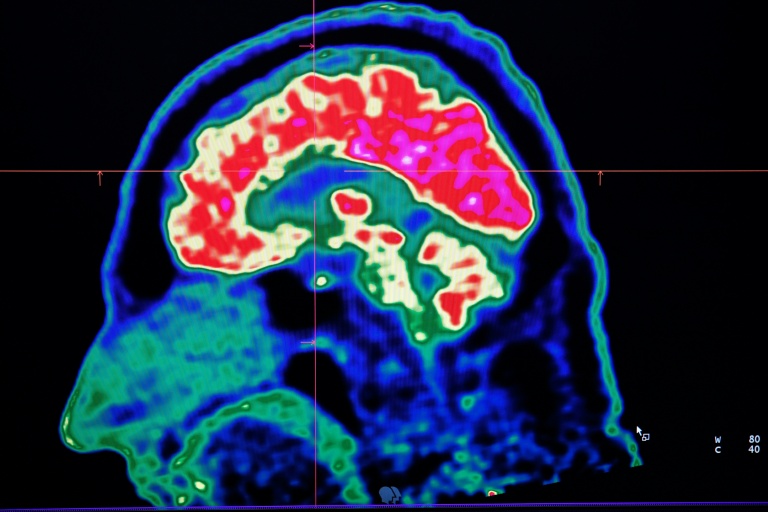

In 2021, health officials in New Brunswick launched an investigation involving 48 patients with a range of neurological symptoms but no apparent common illness. These included muscle spasms, memory loss, hallucinations and balance issues.

Some in the province of less than a million people began describing the condition as a mystery brain disease.

Provincial officials said at the time that the patient group could be suffering from a new disease not previously seen in Canada and began using the term "possible neurological syndrome of unknown cause."

Marrero said that while the condition could not be diagnosed, he believed the patients had elevated levels of certain substances, like herbicides or toxic metals in their systems, suggesting an environmental cause for the illness.